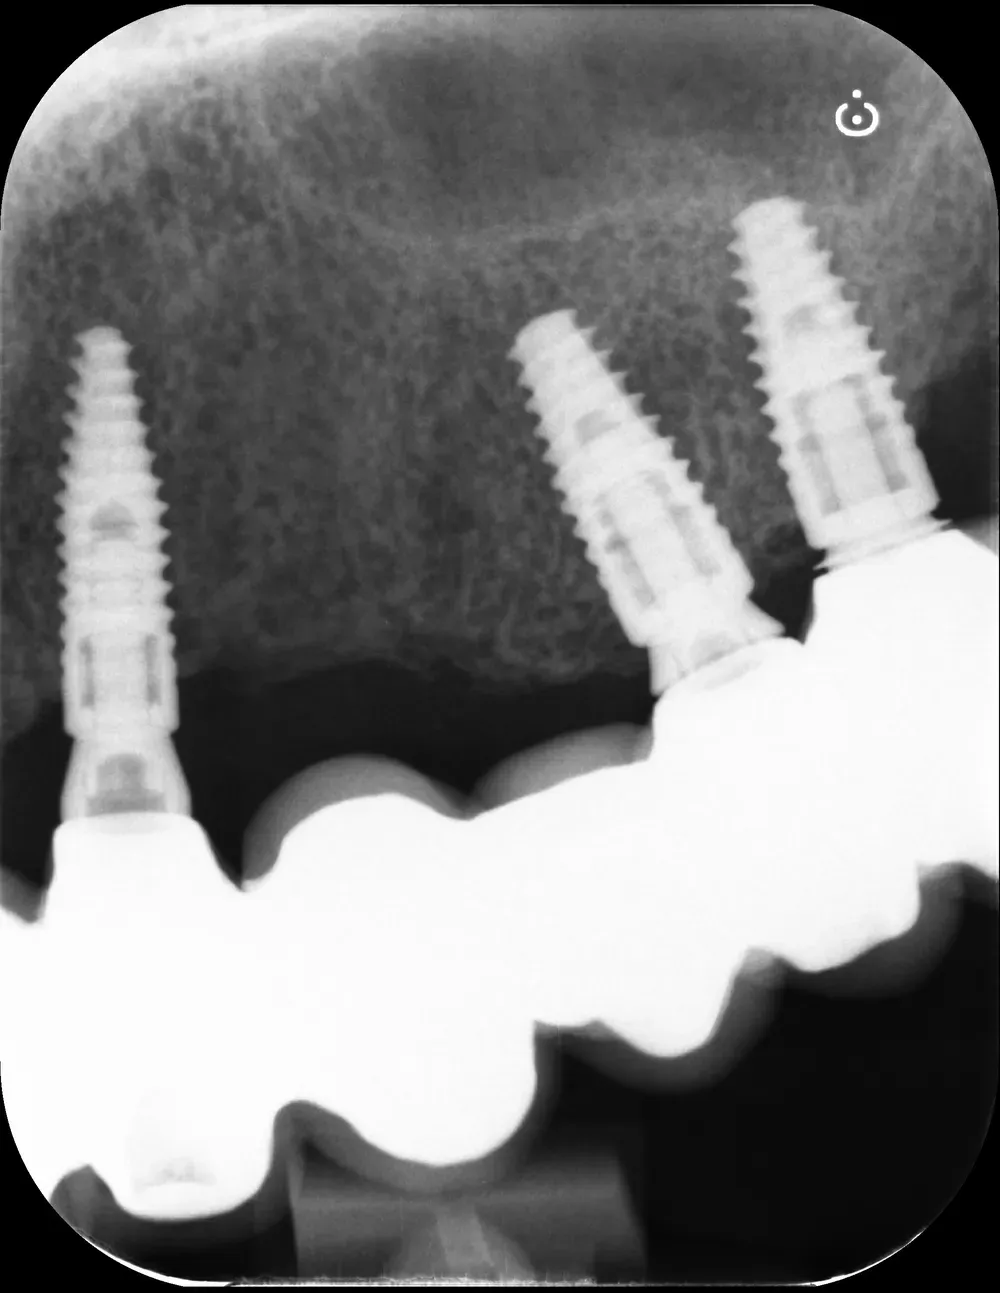

Il controllo a distanza di anni

Al controllo radiografico, sette anni più tardi, gli impianti sono in ottima salute e perfettamente integrati (vedi immagini seguenti).

Francesco viene regolarmente ai controlli, in particolare per le sedute di igiene professionale.